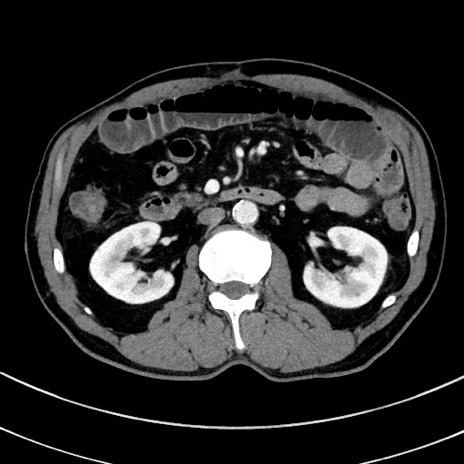

症例8(横断像)

【症例】 60歳代男性

【主訴】 黒色吐物

【現病歴】 4日前から嘔気自覚、2日前の朝食後にも嘔気あり、自分で手で嘔吐反射起こし嘔吐したところ血が混ざっていたため受診。

【既往歴】 5年前汎発性腹膜炎を伴う急性虫垂炎で手術、高血圧、前立腺肥大症、高脂血症

【身体所見】 腹部正中に手術癩痕あり 腹部平坦・軟圧痛なし膨満感あり

【データ】WBC 8400、CRP 4.54